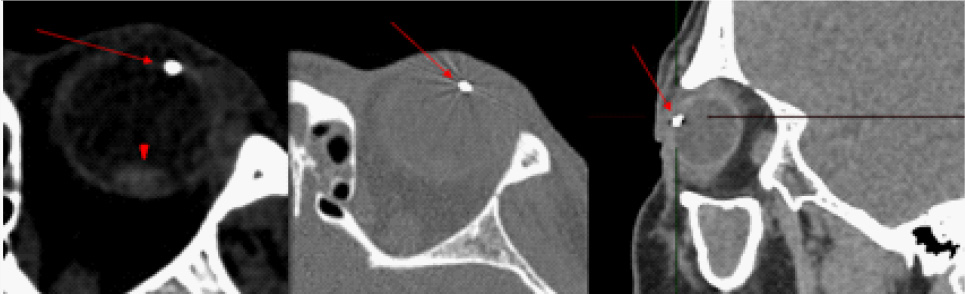

На компьютерной томограмме в передней камере глаза отмечалась структура диаметром 3,7 мм, металлической плотности до 3000 HU (Hounsfield Units) (рис. 4).

Рис. 4. Компьютерная томограмма области орбиты. ВГИТ указано стрелкой, хрусталик на глазном дне – наконечником стрелки

В заднем сегменте глазного яблока отмечалась дополнительная структура диаметром 8,5 мм, плотность 92 HU. В области сканирования левая верхнечелюстная пазуха тотально заполнена содержимым, ячейки решетчатой кости с субтотальным заполнением просвета (рис. 5).